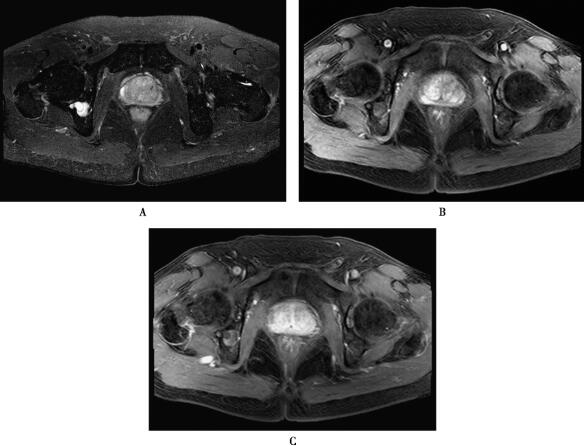

图1 前列腺癌

T2WI(A)发现前列腺右侧外周带的片状低信号,增强扫描动脉期(B)病灶显著强化,静脉期强化(C)程度有所降低